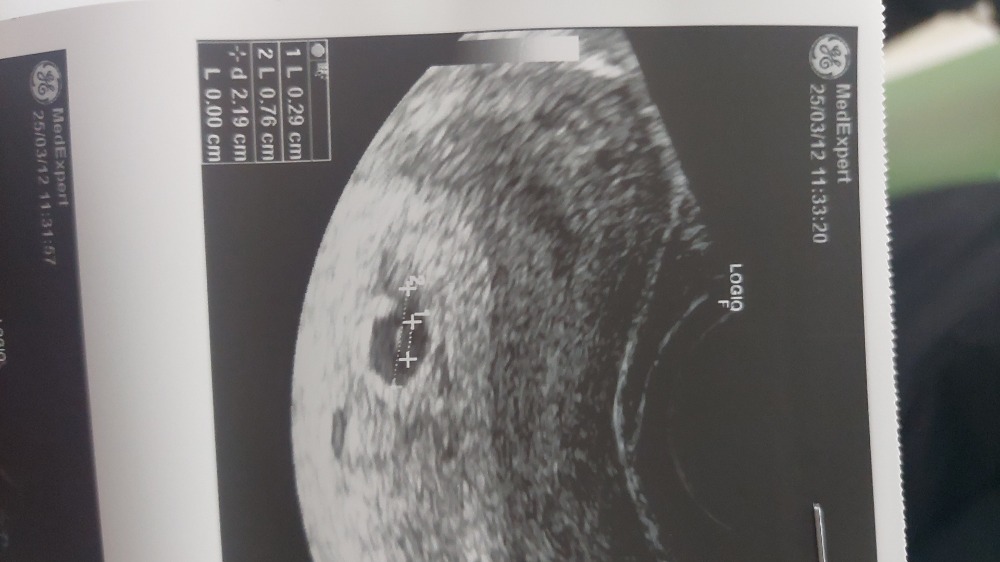

Медленно ростет хгч ХГЧ 1000, плодного яйца нет